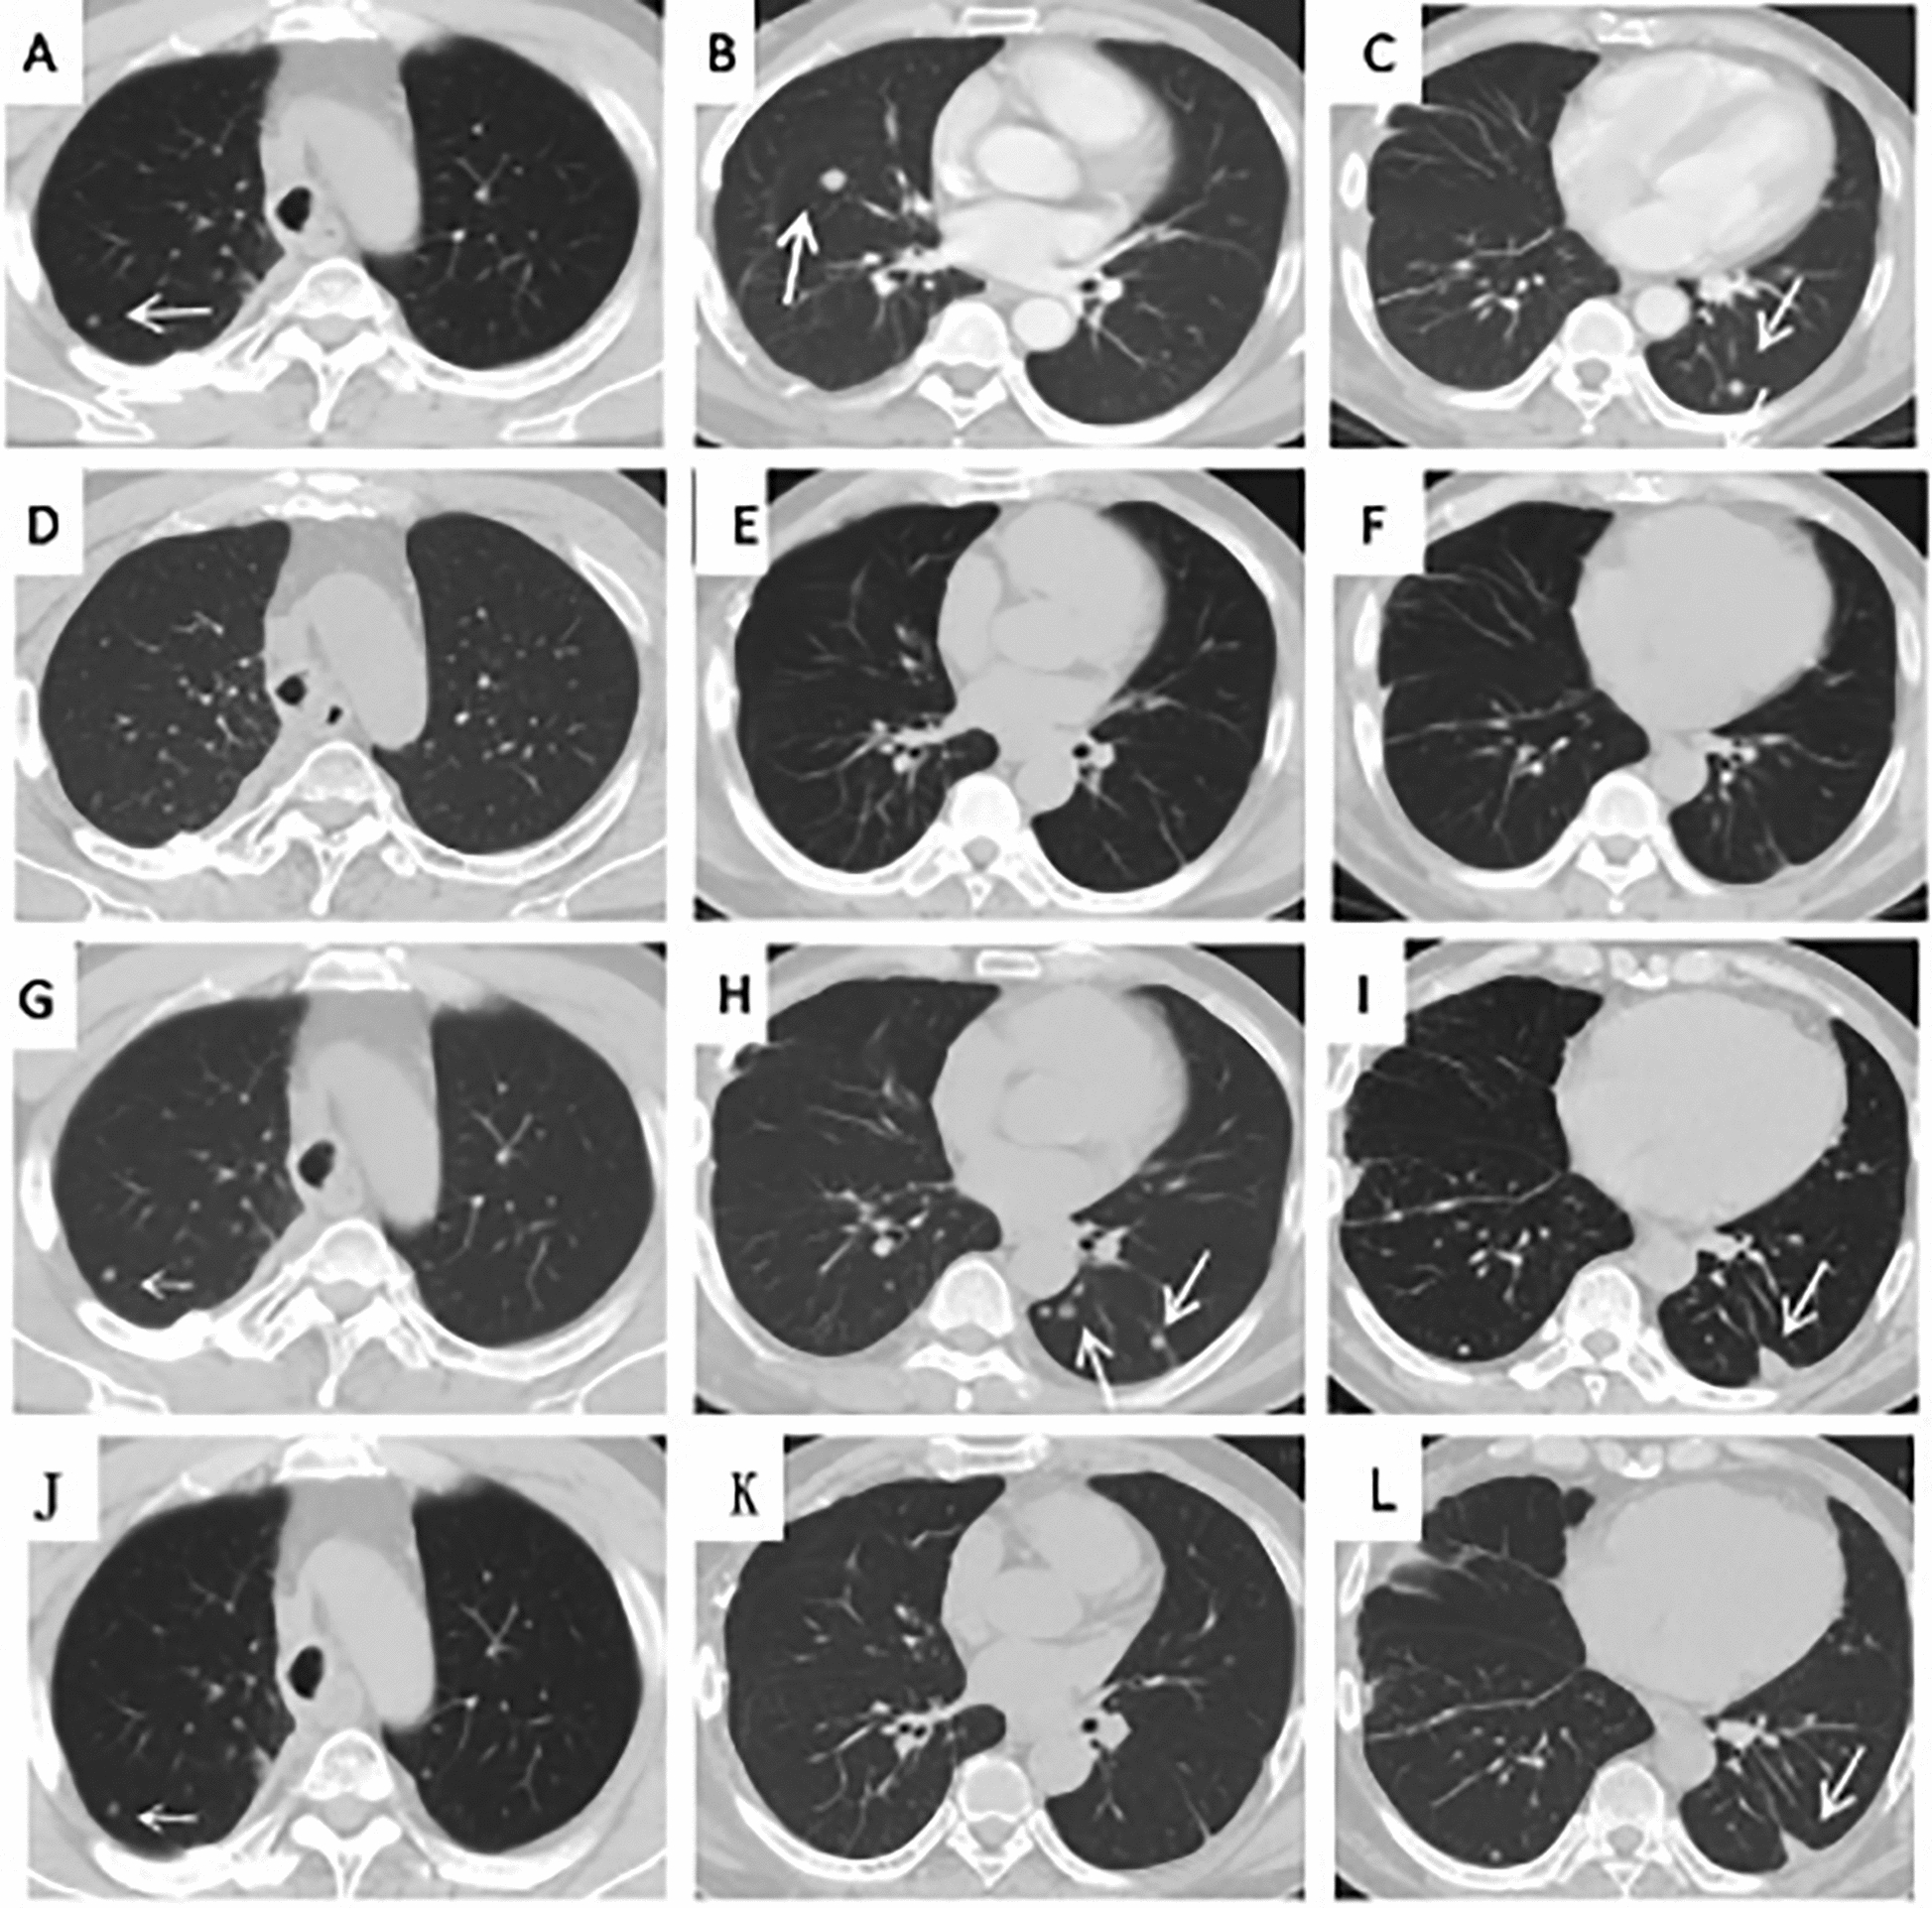

Case presentation: We report a 42-year-old treatment-naïve Chinese male patient with metastatic tracheal adenoid cystic carcinoma harboring a MET p.D1010Y and KRAS p.G12C comutation. The patient responded well to the MET inhibitor crizotinib and MEK inhibitor trametinib combination therapy, but had progression when he discontinued trametinib because of grade III rashes on the face and trunk. With the reintroduction of trametinib with a dose reduction, his metastatic lesions shrank after 2 months of therapy.